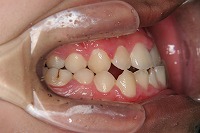

18歳7か月

右

反対咬合と下顎が出ている事を主訴に来院された、初診時18歳1か月の男性です。診断「上顎骨の後方位による骨格性反対咬合」非抜歯での矯正治療と、下顎を後退させる外科手術を併用して治療を行いました。